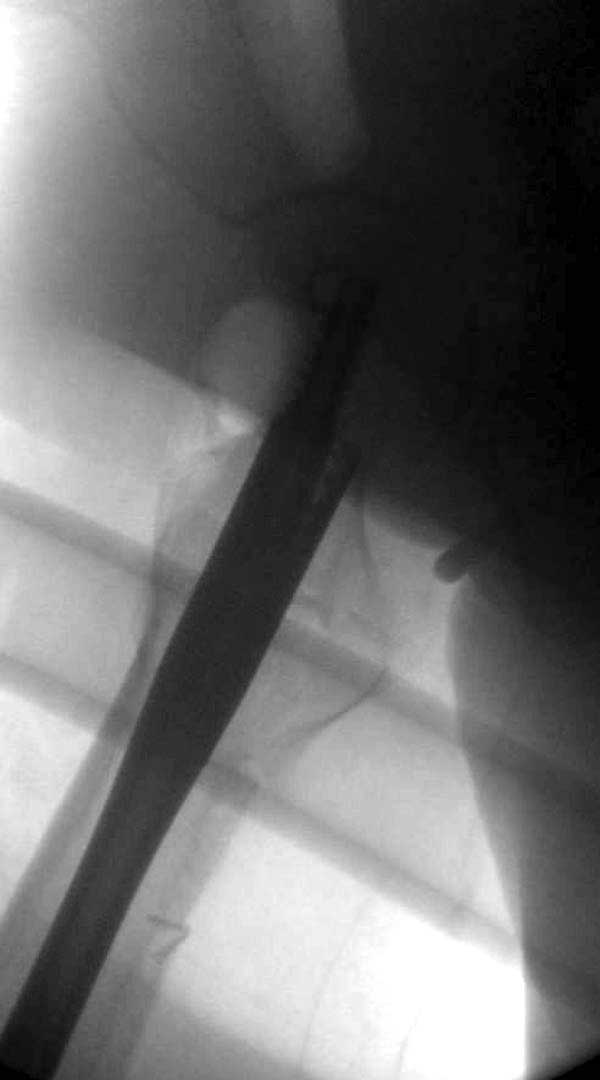

Такие “чужие осложнения” встречаются у всех и представляю банальный случай, который шаг за шагом показано как перерос в более сложный процесс... Больная 70 лет, множественные ко-морбидности, чрезвертельный перелом первоначально фиксирован Гамма 3. Осложнение в течение 6 недель, ревизия тотальной артропластикой и во время установки ножки обнаружена трещина диафиза (17), из малого доступа фиксация алло-графтом.

Обычно после чрезвертельных переломов, за исключением молодых, у пожилых остается нестабильность при движении. Часто падают и после 3х мес. в результате падения обнаружен перипротезный перелом (22-23), который зафиксирован Синтез пластиной.